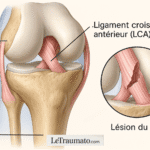

Lésions méniscales ou ligamentaires non traitées

Une lésion du ménisque, même ancienne, peut se réveiller en position allongée. Le genou devient douloureux lors d’un mouvement involontaire la nuit. Les douleurs ligamentaires post-traumatiques sont aussi fréquentes après une entorse mal soignée.

- IRM : détecte les lésions ligamentaires ou méniscales.